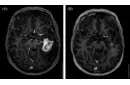

Beyinde kitle ameliyatı, genellikle tümörler, kist veya diğer anormal oluşumların cerrahi olarak çıkarılması amacıyla yapılan bir işlemdir. Bu tür bir ameliyat, beyin dokusuna doğrudan müdahale gerektiği için belirli riskler taşır ve sonrasında hastalar için çeşitli zorluklar ortaya çıkabilir. İşte bu makalede, beyin kitle ameliyatının riskleri ve sonrası hakkında detaylı bir inceleme yapılacaktır. 1. Beyin Kitle Ameliyatının Riskleri Beyin kitle ameliyatı, birçok risk barındırır. Bu riskler arasında şunlar bulunmaktadır:

4. Potansiyel Komplikasyonlar Ameliyat sonrası komplikasyonlar, hastanın genel sağlığını etkileyebilir. Bunlar arasında: